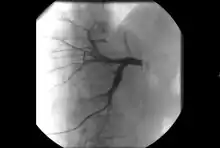

- Angiography: Imaging the blood vessels to look for abnormalities with the use of various contrast media, including iodinated contrast, gadolinium based agents, and CO2 gas.[3]